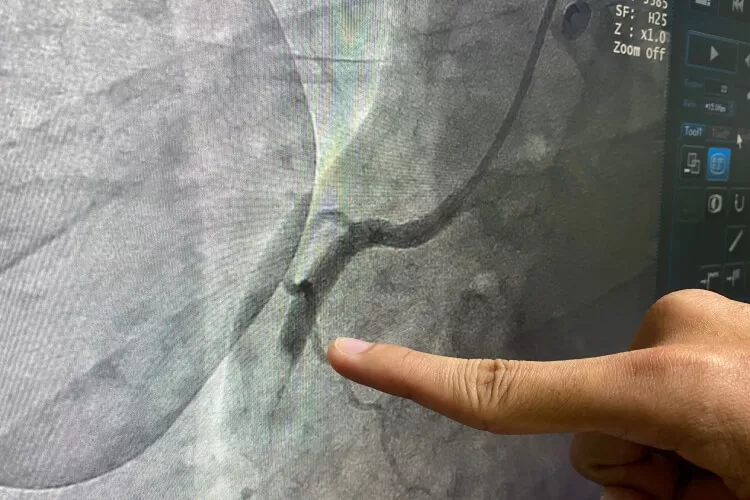

Na počátku studie THEMIS byla kromě výše uvedených cílů předem specifikovaná subanalýza THEMIS-PCI, která sledovala účinek DAPT (tikagrelor + ASA) u podskupiny pacientů s DM2 a ICHS, kteří již v minulosti podstoupili perkutánní koronární intervenci (PCI). Šlo o 58 % nemocných zařazených do studie THEMIS (n = 11 154).

U této předdefinované populace pacientů byl zaznamenán jednoznačně příznivý efekt DAPT. Po 36 měsících totiž došlo k 15% snížení rizika výskytu primárního kompozitního cíle složeného z KV úmrtí, IM a CMP (6,5 vs. 7,7 %; p = 0,013), zatímco ve skupině diabetiků s ICHS bez předchozí PCI žádný statisticky významný rozdíl pozorován nebyl (7,4 vs. 7,5 %; p = 0,76). Ještě větší benefit z podání tikagreloru byl ve studii THEMIS-PCI zaznamenán u podskupiny pacientů s historií koronárního stentingu bez rozlišení typu stentu (HR 0,81; p = 0,003), přičemž nejvíce profitovali nemocní s implantací lékového stentu v anamnéze (HR 0,79; p = 0,008).

Dalším významným příspěvkem k probíhající debatě o efektivním a současně bezpečném využití kombinace antitrombotik a protidestičkové léčby rizikových pacientů, kteří podstoupili úspěšnou perkutánní koronární intervenci (PCI), se stala studie TWILIGHT. Investigátoři v ní sledovali nemocné s vysokým rizikem trombotických komplikací po PCI, přičemž je randomizovali k léčbě DAPT pomocí tikagreloru a ASA nebo monoterapii tikagrelorem a placebem.

Mezi angiografickými kritérii byla ICHS s postižením více tepen (cca 65 % pacientů), PCI s implantací stentu o minimální délce 30 mm, trombotická cílová léze, bifurkační léze (cca 12 %), nemoc kmene (cca 8 %) nebo proximální RIA (cca 75 %) či kalcifikovaná léze ošetřená aterektomií (cca 14 %).